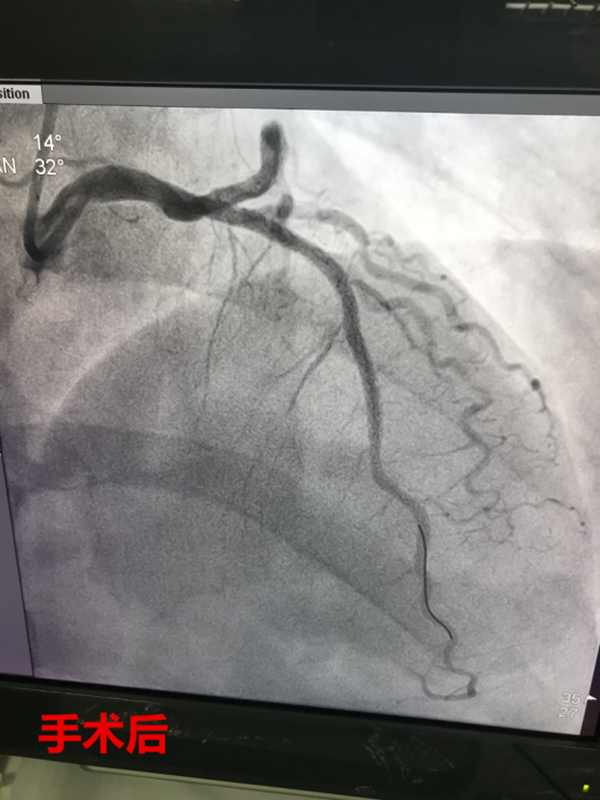

11時12分,路艷主治醫(yī)師護送患者繞行急診科及CCU,直達介入室。徐曉輝主任、耿蓬勃、師軍峰副主任醫(yī)師以及介入室護士郭紀文、于永利、霍貝貝等人員立即就位,手術(shù)開始,穿刺、造影、導絲通過、球囊擴張、支架植入,為患者實施的急診手術(shù)一切都緊張有序的進行……11時45分,手術(shù)順利完成,DtoB時間(患者進入醫(yī)院大門至PCI介入手術(shù)球囊擴張的時間)僅僅26分鐘,遠遠超出了國家對胸痛患者DtoB的時間要求(國家胸痛中心DtoB時間要求<90分鐘)。